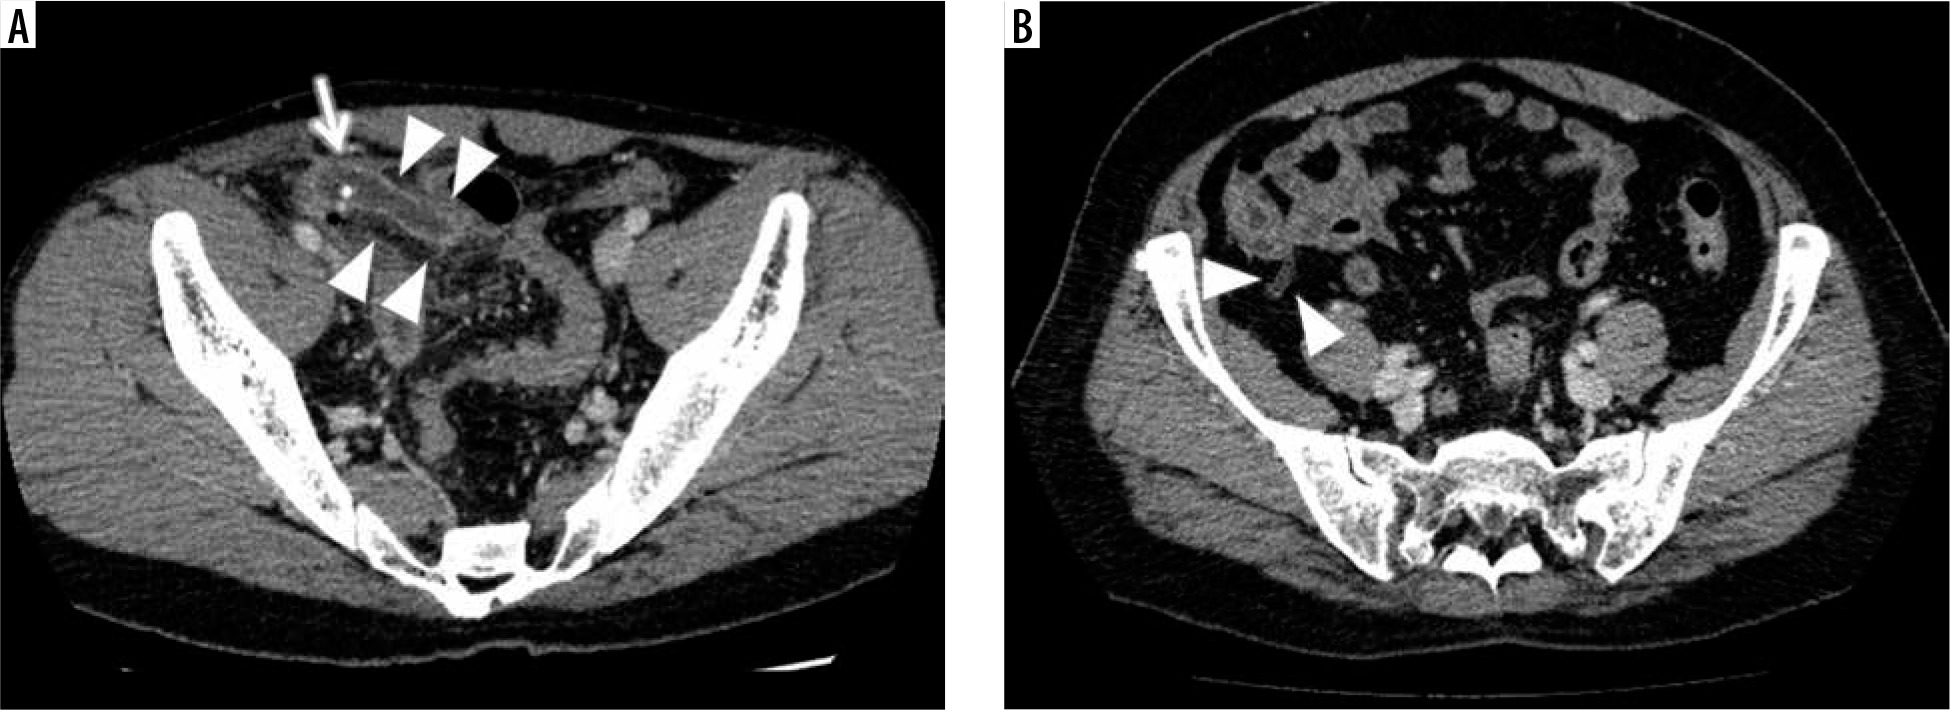

Figure 3

Representative examples of CT images in the appendicitis and control groups. A) Contrast-enhanced abdominal CT of a 32-year-old male in the appendicitis group shows an enlarged appendix with thickened wall enhancement (arrowheads) in conjunction with fluid and an appendicolith inside (arrow) at the right lower quadrant in the abdomen. B) The CECT of a 54-year-old female in the control group shows a normal gas-filled appendix with non-enhanced thin wall (arrowheads) at the apex of the cecum